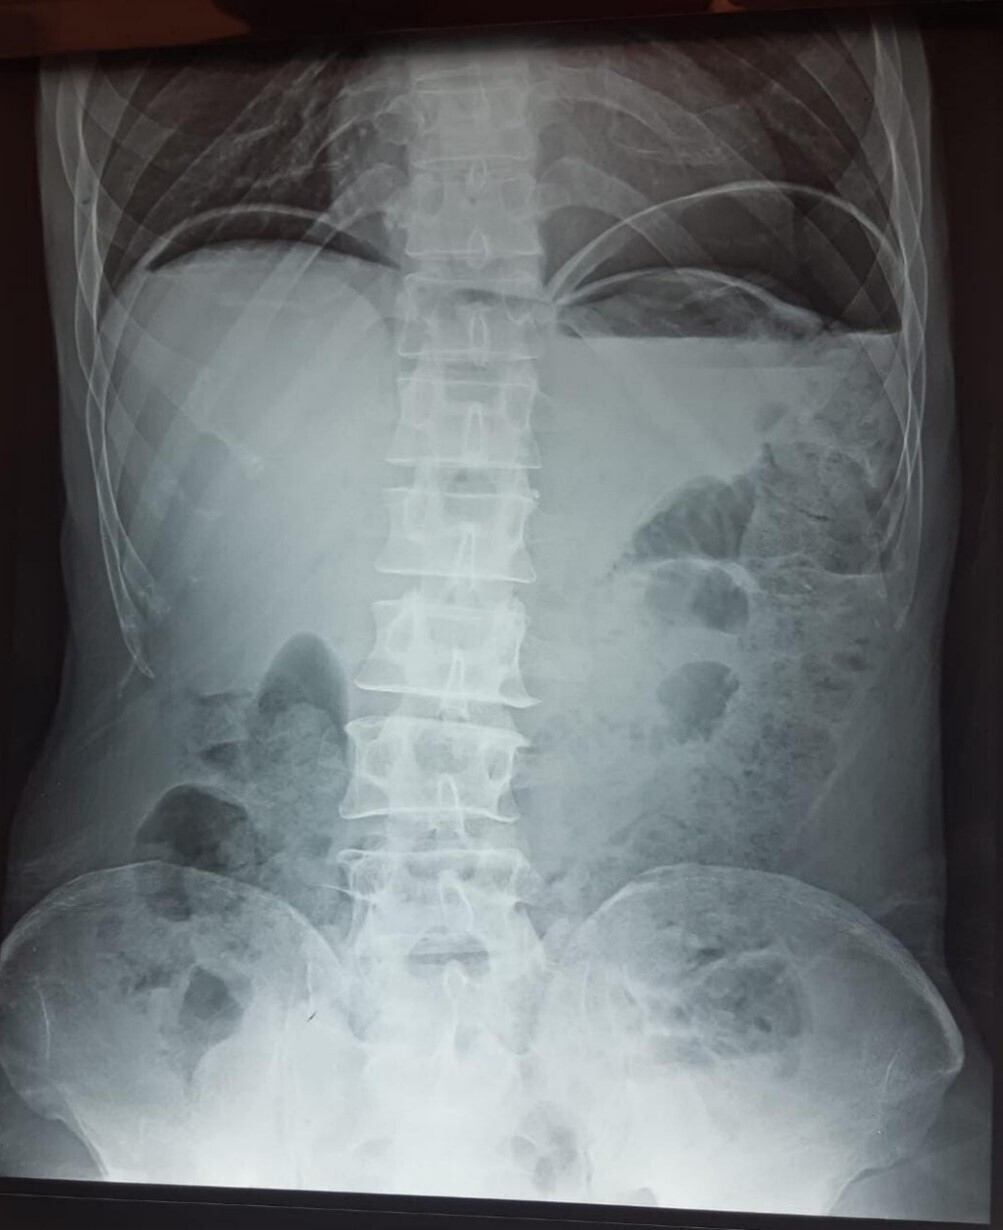

Vous demandez un abdomen sans préparation (ASP) en urgence.

Chez ce patient, c’est une péritonite par perforation d’ulcère gastro-duodénal (UGD). Le diagnostic est avant tout clinique. Le début de la douleur (< 12 h) est épigastrique, puis devient diffuse. À l’interrogatoire, on retrouve généralement les antécédents d’UGD ou la prise d’AINS. Au début, il n’y a pas de sepsis, ce qui explique l’absence du syndrome infectieux. La présence du pneumopéritoine à l’ASP (croissant gazeux) est pathognomonique de perforation d’organe creux. Mais son absence n’élimine pas le diagnostic. ATTENTION : la suspicion d’ulcère perforé est une contre-indication absolue à l’endoscopie œsogastroduodénale ! (risque d’aggravation du pneumopéritoine par l’insufflation +++).2

Chez ce patient, c’est une péritonite par perforation d’ulcère gastro-duodénal (UGD). Le diagnostic est avant tout clinique. Le début de la douleur (< 12 h) est épigastrique, puis devient diffuse. À l’interrogatoire, on retrouve généralement les antécédents d’UGD ou la prise d’AINS. Au début, il n’y a pas de sepsis, ce qui explique l’absence du syndrome infectieux. La présence du pneumopéritoine à l’ASP (croissant gazeux) est pathognomonique de perforation d’organe creux. Mais son absence n’élimine pas le diagnostic.

ATTENTION : la suspicion d’ulcère perforé est une contre-indication absolue à l’endoscopie œsogastroduodénale ! (risque d’aggravation du pneumopéritoine par l’insufflation +++).2